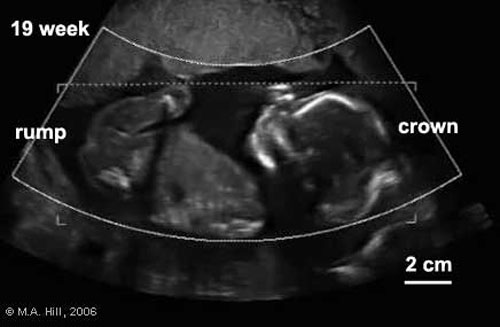

Gli esami prenatali – I test di screening per diagnosticare aventuali anomalie fetali sono cinque: indagine ecografica al primo appuntamento, test sierologici per la sindrome di Down, amniocentesi ed analisi dei villi corali solo per chi è a rischio, indagine ecografica per anomalie fetali. Insomma, il modello fissato dal Ministero cambia la trafila e fissa paletti e criteri precisi: si sottopongono all’amniocentesi e alla villocentesi solo le donne a rischio, cioè quelle risultate positive al test combinato eseguito tra 11esima e 13esima settimana. Questo esame incrocia l’età materna, la traslucenza nucale e gli esami del sangue adatti a indentificare eventuali anomalie, come la sindrome di Down. “Si tratta di introdurre una diversa pratica clinica per individuare le donne a rischio – dice Vittorio Basevi del Ceveas, coordinatore del progetto delle linee guida – facendo dell’amniocentesi e villocentesi delle indagini di secondo livello”.

Le nuove linee guida cercano anche di rispondere agli esperti che lamentano un’eccessiva medicalizzazione della gravidanza. Secondo i dati dell’ultimo rapporto Cedap (Certificato di assistenza al parto), riferiti al 2007, in oltre l’84% delle gravidanze il numero di visite ostetriche effettuate è superiore a quattro, mentre per ogni parto si fa una media di 5,1 ecografie. Le amniocentesi effettuate sono state il 15,4%, e diventano il 43% nelle madri con più di 40 anni.